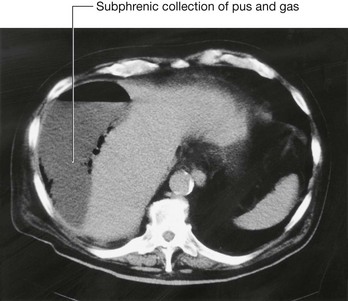

Kidney transplant

Kidney transplantation began in the United States in the 1950s. Since the first transplant, the major problem for kidney transplantation has been tissue rejection. A number of years have passed since this initial procedure and there have been significant breakthroughs in transplant rejection medicine. Renal transplantation is now a common procedure undertaken in patients with end stage renal failure.

Transplant kidneys are obtained from either living or deceased donors. The living donors are carefully assessed, because harvesting a kidney from a normal healthy individual, even with modern day medicine, carries a small risk.

Deceased kidney donors are brain dead or have suffered cardiac death. The donor kidney is harvested with a small cuff of aortic and venous tissue. The ureter is also harvested.

An ideal place to situate the transplant kidney is in the left or the right iliac fossa (Fig. 4.146). A curvilinear incision is made paralleling the iliac crest and pubic symphysis. The external oblique muscle, internal oblique muscle, transverse abdominis muscle, and transversalis fascia are divided. The surgeon identifies the parietal peritoneum but does not enter the peritoneal cavity. The parietal peritoneum is medially retracted to reveal the external iliac artery, external iliac vein, and the bladder. In some instances the internal iliac artery of the recipient is mobilized and anastomosed directly as an end-to-end procedure onto the renal artery of the donor kidney. Similarly the internal iliac vein is anastomosed to the donor vein. In the presence of a small aortic cuff of tissue the donor artery is anastomosed to the recipient external iliac artery and similarly for the venous anastomosis. The ureter is easily tunneled obliquely through the bladder wall with a straightforward anastomosis.

image image

Fig. 4.146 Kidney transplant. A. This image demonstrates an MR angiogram of the bifurcation of the aorta. Attaching to the left external iliac artery is the donor artery for a kidney that has been transplanted into the left iliac fossa. B. Abdominal computed tomogram, in the axial plane, showing the transplanted kidney in the left iliac fossa.

The left and right iliac fossae are ideal locations for the transplant kidney, because a new space can be created without compromise to other structures. The great advantage of this procedure is the proximity to the anterior abdominal wall, which permits easy ultrasound visualization of the kidney and permits Doppler vascular assessment. Furthermore, in this position biopsies are easily obtained. The extraperitoneal approach enables patients to make a swift recovery.